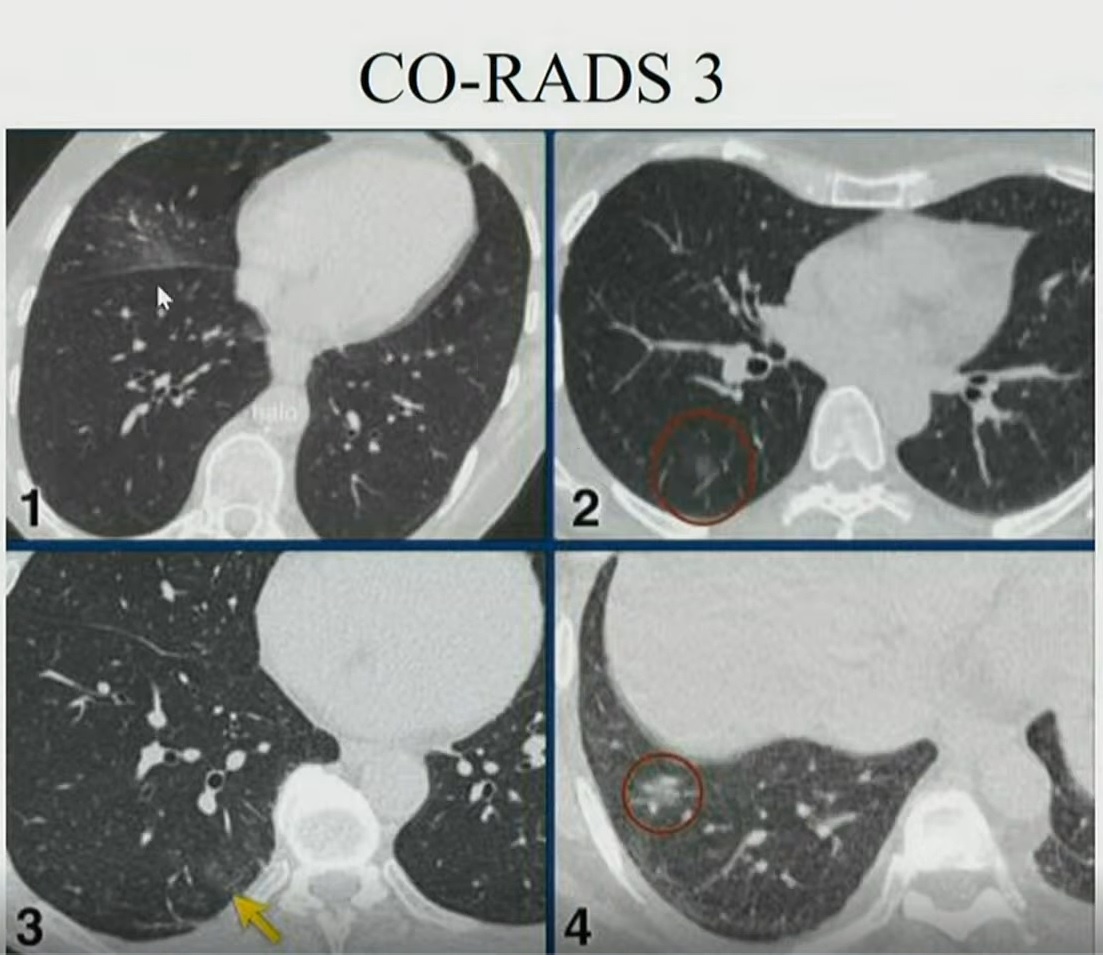

| Hình ảnh phổi của ca mắc Covid-19 thứ 867, các tổn thương cho thấy người này ở giai đoạn đỉnh bệnh. Ảnh: Bệnh viện Đại học Y Hà Nội. |

Ở giai đoạn sớm (0-4 ngày sau khi xuất hiện triệu chứng), X-quang phổi cho thấy kính mờ, hình lát đá, thùy tổn thương ít.

Đến ngày 5, phổi có kính mờ, hình lát đá lan rộng hai bên. Tình trạng này kéo dài đến ngày thứ 8 và được gọi là giai đoạn tiến triển.

Ở giai đoạn đỉnh bệnh (sau 10-13 ngày), phổi của người mắc Covid-19 xuất hiện các vùng đông đặc. Đây cũng là thời điểm cơ quan này bị tổn thương nhiều nhất.

Từ ngày thứ 14 trở đi, nếu bệnh nhân nặng, phổi tiếp tục đông đặc hơn, thậm chí kèm bội nhiễm lan tỏa hai bên. Với những người chữa trị hiệu quả, thời gian này phổi sẽ bước vào giai đoạn thoái triển, dải xơ dưới màng phổi giảm, giãn phế quản ngoại vi.